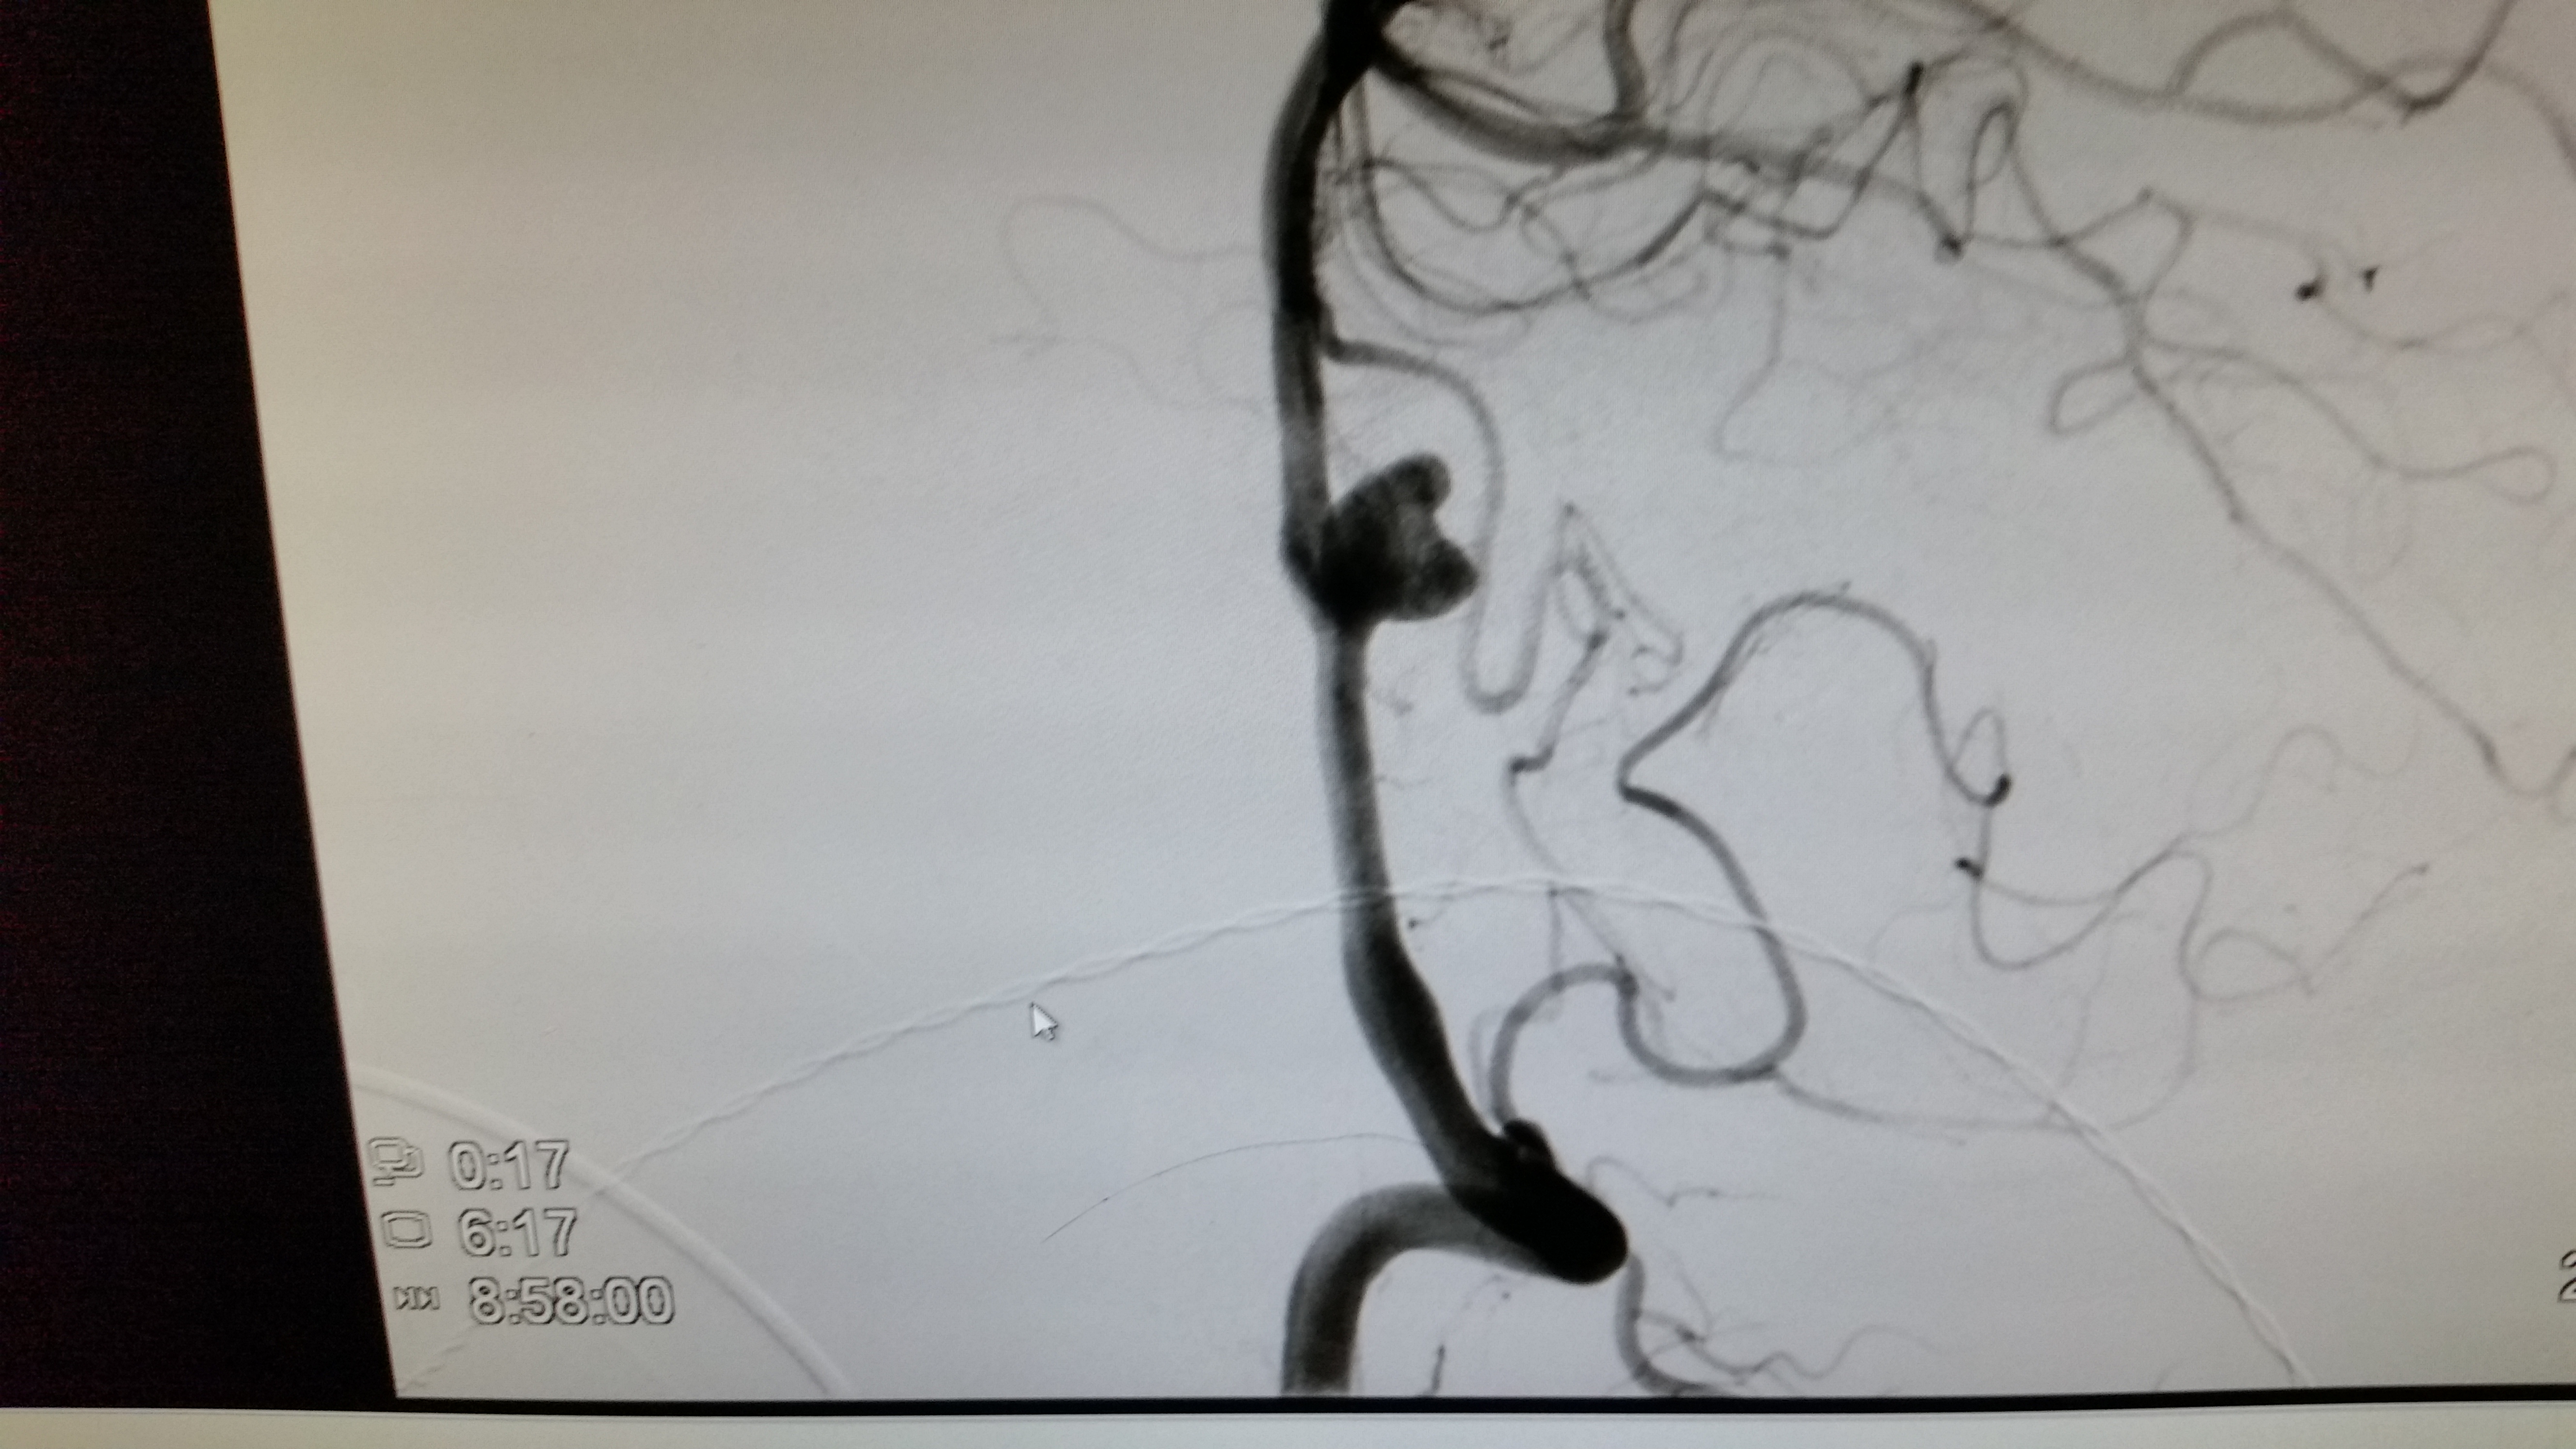

I’ve always been relatively healthy. I have no history of high blood pressure. There is no history of stroke in my family that I’m aware of. There was no advanced notice, no symptoms – it just happened. The short answer: A 1/2″, heart-shaped aneurysm on an artery that supplies blood to my brain, burst in the back of my head, near the base of my skull, and started to fill the lining around my brain with blood. I was told that everything that could have gone right, did. All the things that could have gone terribly wrong, just didn’t. I learned that less than 10% of those who experience this type of brain hemorrhage survive long enough to even get treatment. Of those, less than 10% walk away without some type of negative, long term medical deficiency. It appears that few in my age group (I was 54 y\o) ever experience this type of episode (something like <1% in 135000 men). We don’t know why this happened to me. Why it happened when it did or where it did. God knows. All I know is if it had occurred 20 minutes later I might have been driving my friend back to the office. The next day, I might have been assisting our team on a ladder or hydraulic lift installing projectors or preparing the stage for Christmas Eve rehearsals. Even that morning I could have been on the stairs at home or out in the neighborhood walking the dog. The outcome could have been far more tragic for me and for others. I do believe God protected people that day.

Doctors say that the large aneurysm may have been there my entire life. I could have been born with it. I’m told that it could have a genetic link or it could have just been a total anomaly. Thankfully I survived that first night in ICU and the aneurysm was permanently sealed early the next morning by a team of neurologists using one of two available procedures. In my case the surgeons threaded a line thru an artery up to my brain and filled the aneurysm with a “coil” of about 6″ of thin “wire” filament to permanently block the flow of blood thru it and keep it from being a problem again.